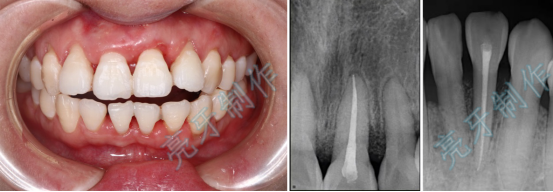

病例三:牙齿嵌入牙槽骨,松动明显,经过治疗,稳定了,也恢复了外形。